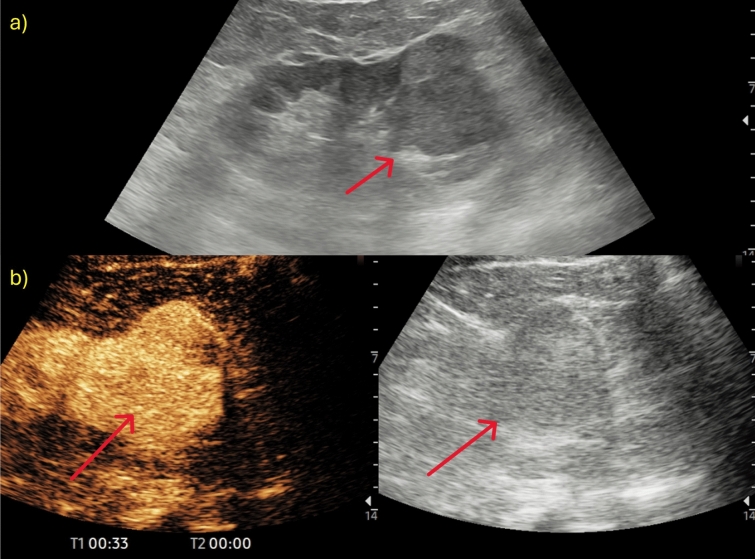

对比增强超声(CEUS)已成为检测和表征实性肾脏病变的重要工具,补充了传统的b型超声,后者往往难以区分实性和囊性肿块。超声造影通过提供详细的血管化信息来提高诊断的准确性,有助于识别潜在的恶性实体病变,并区分假肿瘤和实体肿块。此外,超声造影使用的造影剂即使对肾病患者也是安全的,并且可以不考虑肾功能,使其成为肾脏成像的有利方法。在这篇叙述性综述中,根据欧洲超声医学和生物学协会联合会的指南,作者展示了其主要适应症:在移植肾患者中诊断不确定的肾脏病变,监测非手术病变,诊断炎症-感染性肾脏病变,评估手术床上的晚期肾脏病变和肿块。

Contrast-enhanced ultrasound (CEUS) has become an important tool for the detection and characterization of solid renal lesions, complementing traditional B-mode US, which often struggles to distinguish between solid and cystic masses. CEUS enhances diagnostic accuracy by providing detailed vascularization information, helping to identify potentially malignant solid lesions and differentiate between pseudotumours and solid masses. Moreover, CEUS employs a contrast agent that is safe even for nephropathic patients and can be used without concern for kidney function, making it an advantageous method for renal imaging. In this narrative review, following the European Federation of Societies for Ultrasound in Medicine and Biology guidelines, the authors show its main indications: characterizing indeterminate renal lesions in patients with transplanted kidney, monitoring non-surgical lesions, diagnosing inflammatory-infectious renal pathologies, and assessing advanced renal lesions and masses in the surgical bed.